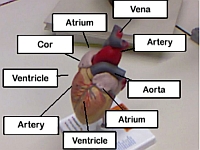

Christina Schwarz-Gsaxner, Markus Perz, Gijs Luijten, Jens Kleesiek, Dieter Schmalstieg, Jan Egger:

MultiAR: A Collaborative Augmented Reality Platform for Biomedical Education

In Proc. IEEE Engineering in Medicine and Biology, July 2024.